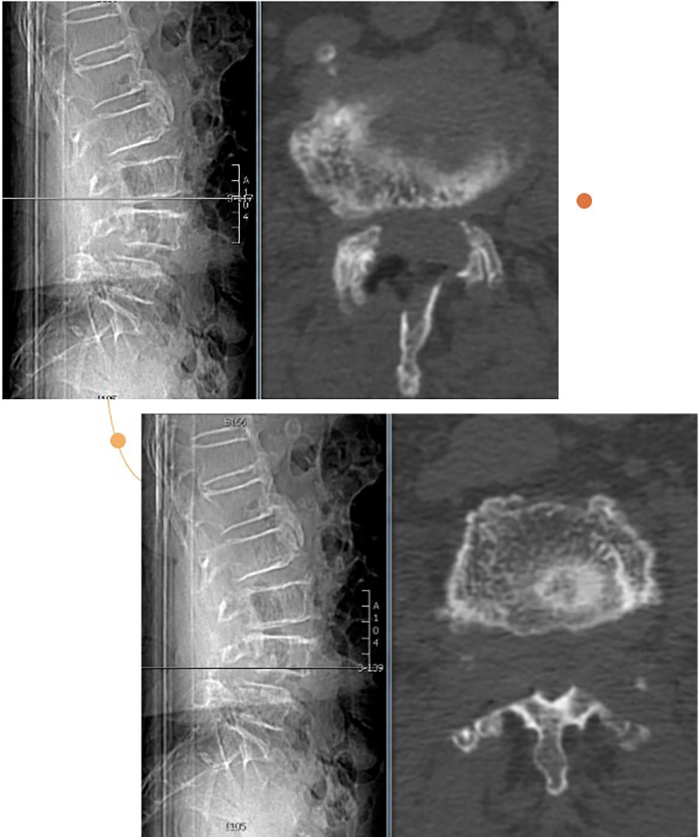

陈瑞松副主任医师接诊后,经过详细询问病史、全面查体,并结合影像学检查,诊断为腰椎椎管重度狭窄症。考虑到张阿婆年事已高,有高血压、冠心病、糖尿病、骨质疏松病史,陈瑞松副主任医师建议其采用微创手术治疗。据介绍,相较于常规开放手术,脊柱微创手术有创伤小、出血少、恢复快等优点,是高龄患者的福音。

术前影像

经过详细的术前评估和完善的术前准备,陈瑞松带领团队为张阿婆进行一个节段的单侧入路双侧减压(ULBD)手术及一个节段的双侧入路270度减压手术,仅切开了三个7毫米的小切口,一个多小时就顺利完成手术。